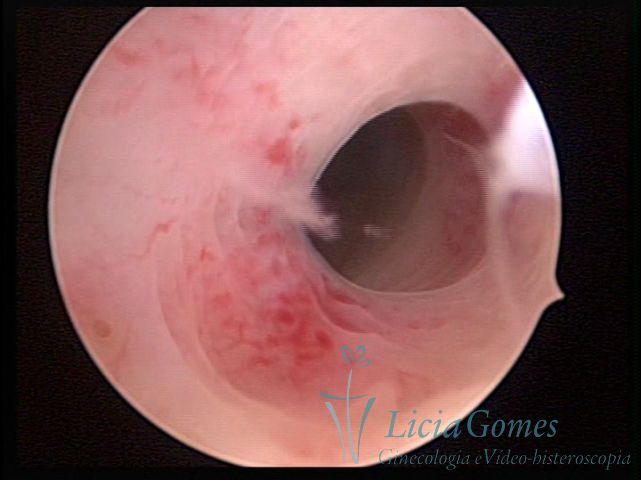

Terceira porção ou porção superior

Apresenta a mucosa com a superfície lisa e pouco vascularizada até a altura do orifício interno